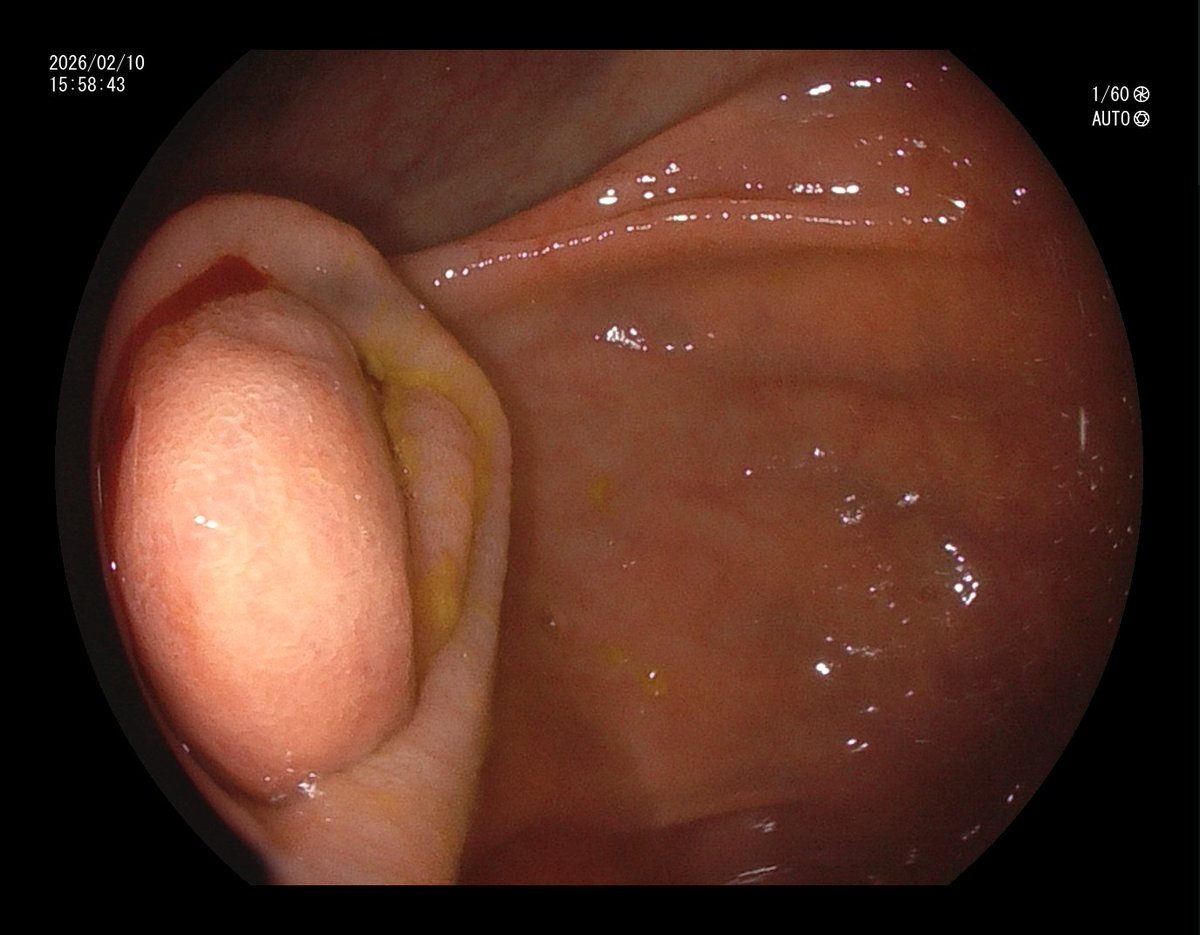

1. Antrum, low grade dysplasia. Removed via ESD. Specimen 43x32mm / dysplasia 20x13mm. R0